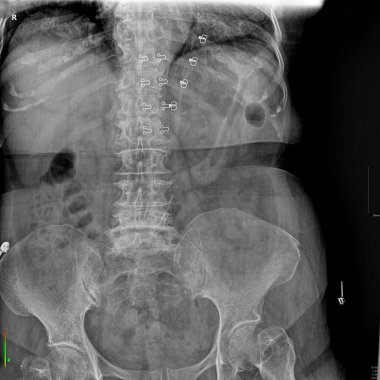

Sırt ve kereste omurgasının röntgen ışınları spondilotik değişimleri, sırt ve kereste dikenlerinin düzleştirilmesini, omurgalar arası disk alanlarının bozulmamış olduğunu, sırt ve kereste dikenlerinin Spondylosis 'inin bozulmamış olduğunu gösterir.